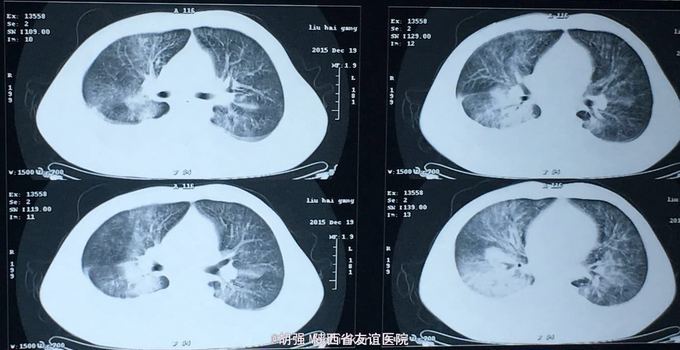

查体:口唇无发绀,咽充血,双侧扁桃体2度大,表面可见脓胎。两肺呼吸音粗糙,可闻及管状呼吸音。余查体无明显异常。 辅助检查:血常规提示白细胞及血小板明显低于正常值,肝功提示转氨酶升高。凝血系列:PT、APTT时间明显延长。T sport试验弱阳性。10月份胸部CT平扫未见明显异常。10月26日及12月12日胸片未见明显异常。12月19日胸部CT提示:两肺斑片状阴影,两侧胸腔积液。